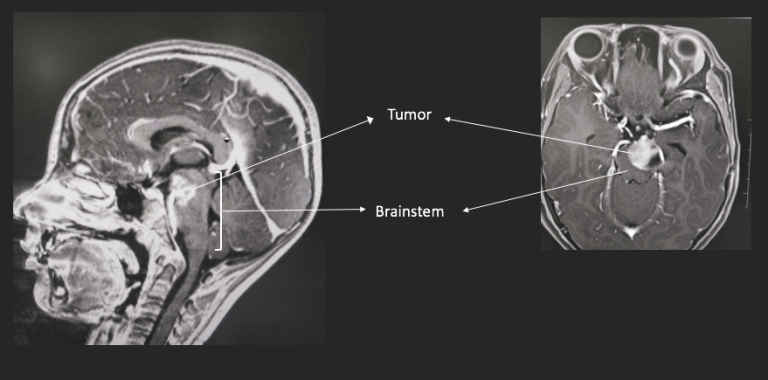

神经胶质瘤是由脑内称为胶质细胞的一组细胞引起的肿瘤。有不同类型的神经胶质细胞,每种神经胶质细胞都为大脑提供重要的支持功能。脑干神经胶质瘤可由称为星形胶质细胞、少突胶质细胞或多种细胞混合物的神经胶质细胞组成,它们发生在脑干中,脑干是大脑后部的区域,是人体许多功能控制中心所在的区域,例如负责呼吸。

脑干神经胶质瘤常发生于儿童,但可在任何年龄的患者中发展。尽管它们在成年人中相对很少见,但往往在患者三十多岁的时候出现。症状取决于肿瘤的大小和位置,但可能包括头痛和脑干所控制的功能问题,例如行走。

对于大多数脑肿瘤,治疗的一步通常是手术切除或切除尽可能多的肿瘤。不幸的是,由于脑干是一个很小的细小区域,充满了重要的解剖结构,因此对于脑干神经胶质瘤患者而言,有时无法进行手术切除。根据肿瘤的大小和位置以及个人健康因素(例如年龄),您的医生可能会或可能不会将手术纳入治疗计划。